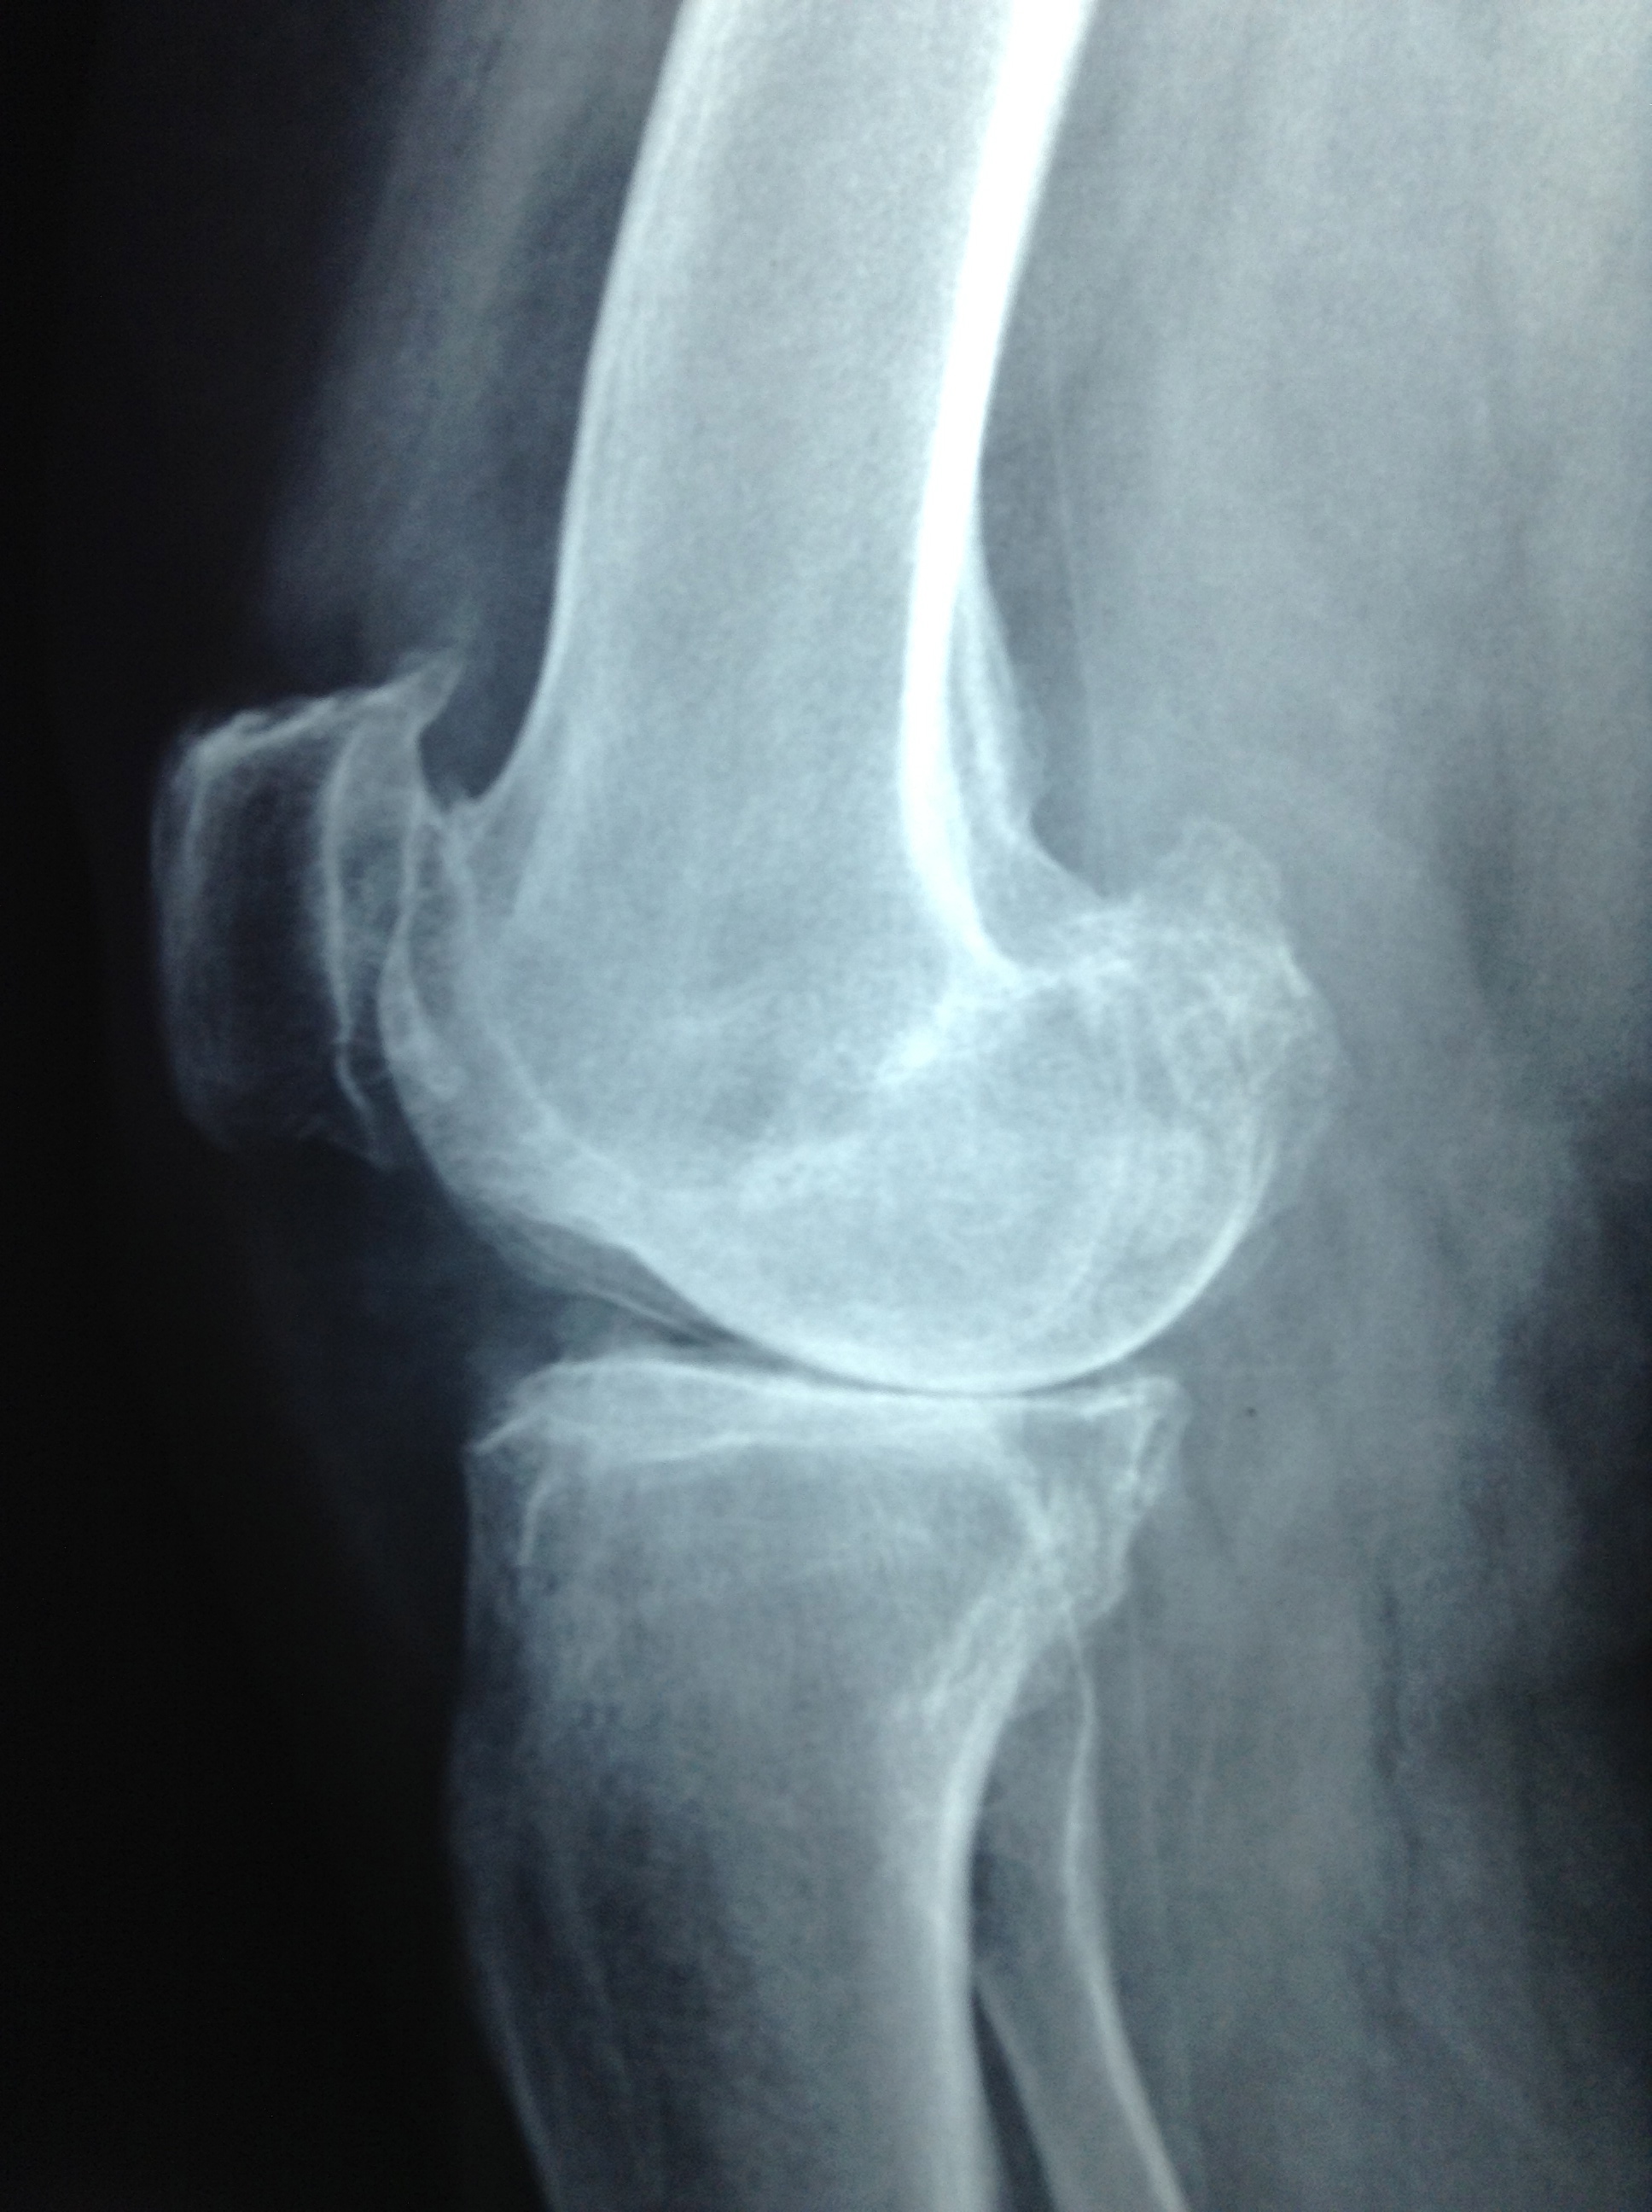

Revision Total Knee Replacement After Infection

• Revision Total Knee Replacement After Infection